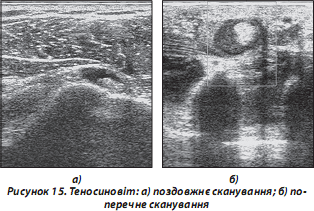

в) хронічний тендиніт: частіше спостерігається в сухожиллях надколінка, ротаторної манжети, ахілловому сухожиллі (рис. 15):

— сухожилля з СО: потовщені, можливі зміни ехоструктури (частіше — зниження ехогенності), часто — помірні явища теносиновіту з накопиченням незначної кількості рідини;